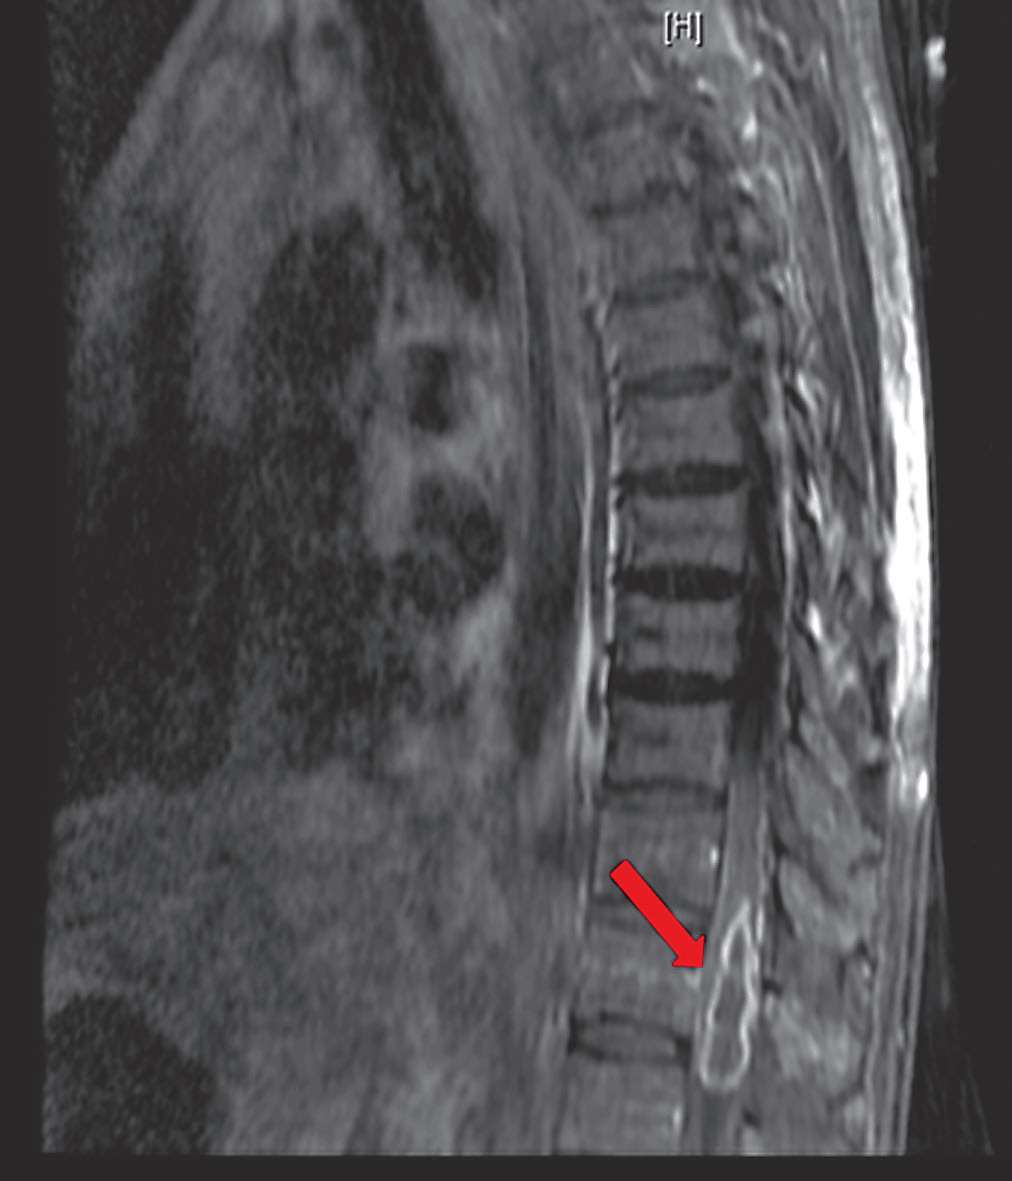

江苏省当地人民医院7月13日行腰穿检查,脑脊液葡萄糖1.33 mmol/L(↓),蛋白质2 644.5 mg/L(↑),脑脊液有核细胞数150×10 6 /L(↑),多核细胞25%。头颅增强MRI(图2-3)示“脑实质内、右侧侧脑室后角内多发异常信号影,考虑感染性病变可能”。入院后予甘露醇、甘油果糖脱水,呋塞米、螺内酯利尿,哌拉西林/他唑巴坦、万古霉素、美罗培南抗感染,地塞米松(共5 mg)抗炎等治疗后,患者症状仍逐渐加重,仍有高热,四肢不自主颤动,进食后有呛咳,大小便失禁,意识障碍进一步加深,呈昏迷状态,双下肢肌力肌张力明显减退,于7月14日出院至我院急诊留观。

图2-3 2018年7月13日头颅增强MRI:脑实质内、右侧侧脑室后角内多发异常信号影,考虑感染性病变可能

患者入院后7月23日行胸腰椎增强MRI(图2-4)见:TH11-L1水平脊髓肿胀,呈斑片状长T2信号,增强呈长环状强化。考虑“TH11-L1水平髓内占位,考虑脓肿可能,肿瘤不除外”。后行腰椎穿刺检查,压力330 mmH 2 O,脑脊液白细胞188×10 6 /L(↑),多核细胞34%,单核细胞66%,脑脊液糖2.4 mmol/L(↓),同步血糖6.8 mmol/L,脑脊液蛋白质3 515 mg/L(↑),脑脊液氯111 mmol/L(↓)(表2-1)。脑脊液隐球菌荚膜多糖抗原乳胶凝集试验阴性,脑脊液细菌和真菌培养均阴性。7月29日脑脊液二代测序回报(图2-5)测得中间链球菌,序列数114。

图2-42018年7月23日胸腰椎增强MRI |